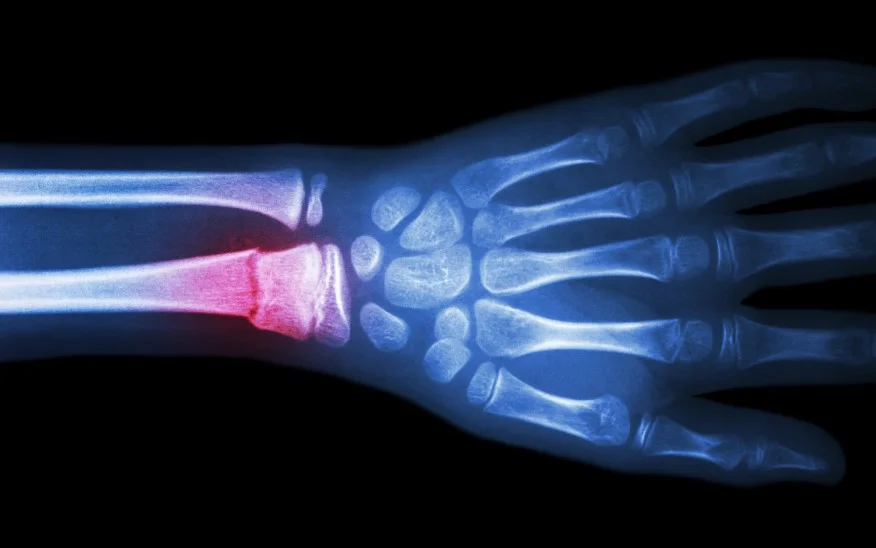

Is Heat Good For Wrist Fracture . The wrist consists of eight small bones that. restricting the movement of a broken bone in your wrist is critical to proper healing. It can happen due to an injury from a fall or when someone excessively bends or twists their wrist. To do this, you'll likely need a splint or a cast. If you suspect you have a broken bone, take first aid steps and get yourself medical attention as soon as possible. A broken wrist, or wrist fracture, typically causes immediate swelling, pain, and tenderness. Applying ice to your injury will help reduce swelling and ease the pain. warmth and redness. a broken wrist, or wrist fracture, is a common injury that can affect any of the 10 bones that make up your forearm and wrist. Your recovery will also include physical therapy to improve movement and strength. signs of a broken wrist, and when to contact a doctor. A bend in your wrist or bone protruding from the skin. a wrist fracture is a break in one of the bones that form the wrist. If you have a broken wrist, you will probably need a cast, splint or sling. Do this until the swelling subsides.